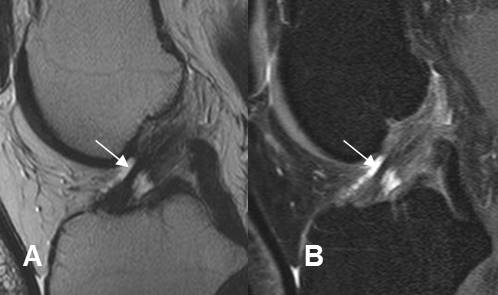

Fig 164. Esguince grado I.

A: RM sagital en T1, B: RM sagital en T2 y C: RM coronal en STIR. Alteración de la señal en el tercio distal del LCA, pero sin ruptura de fibras, por esguince GI.